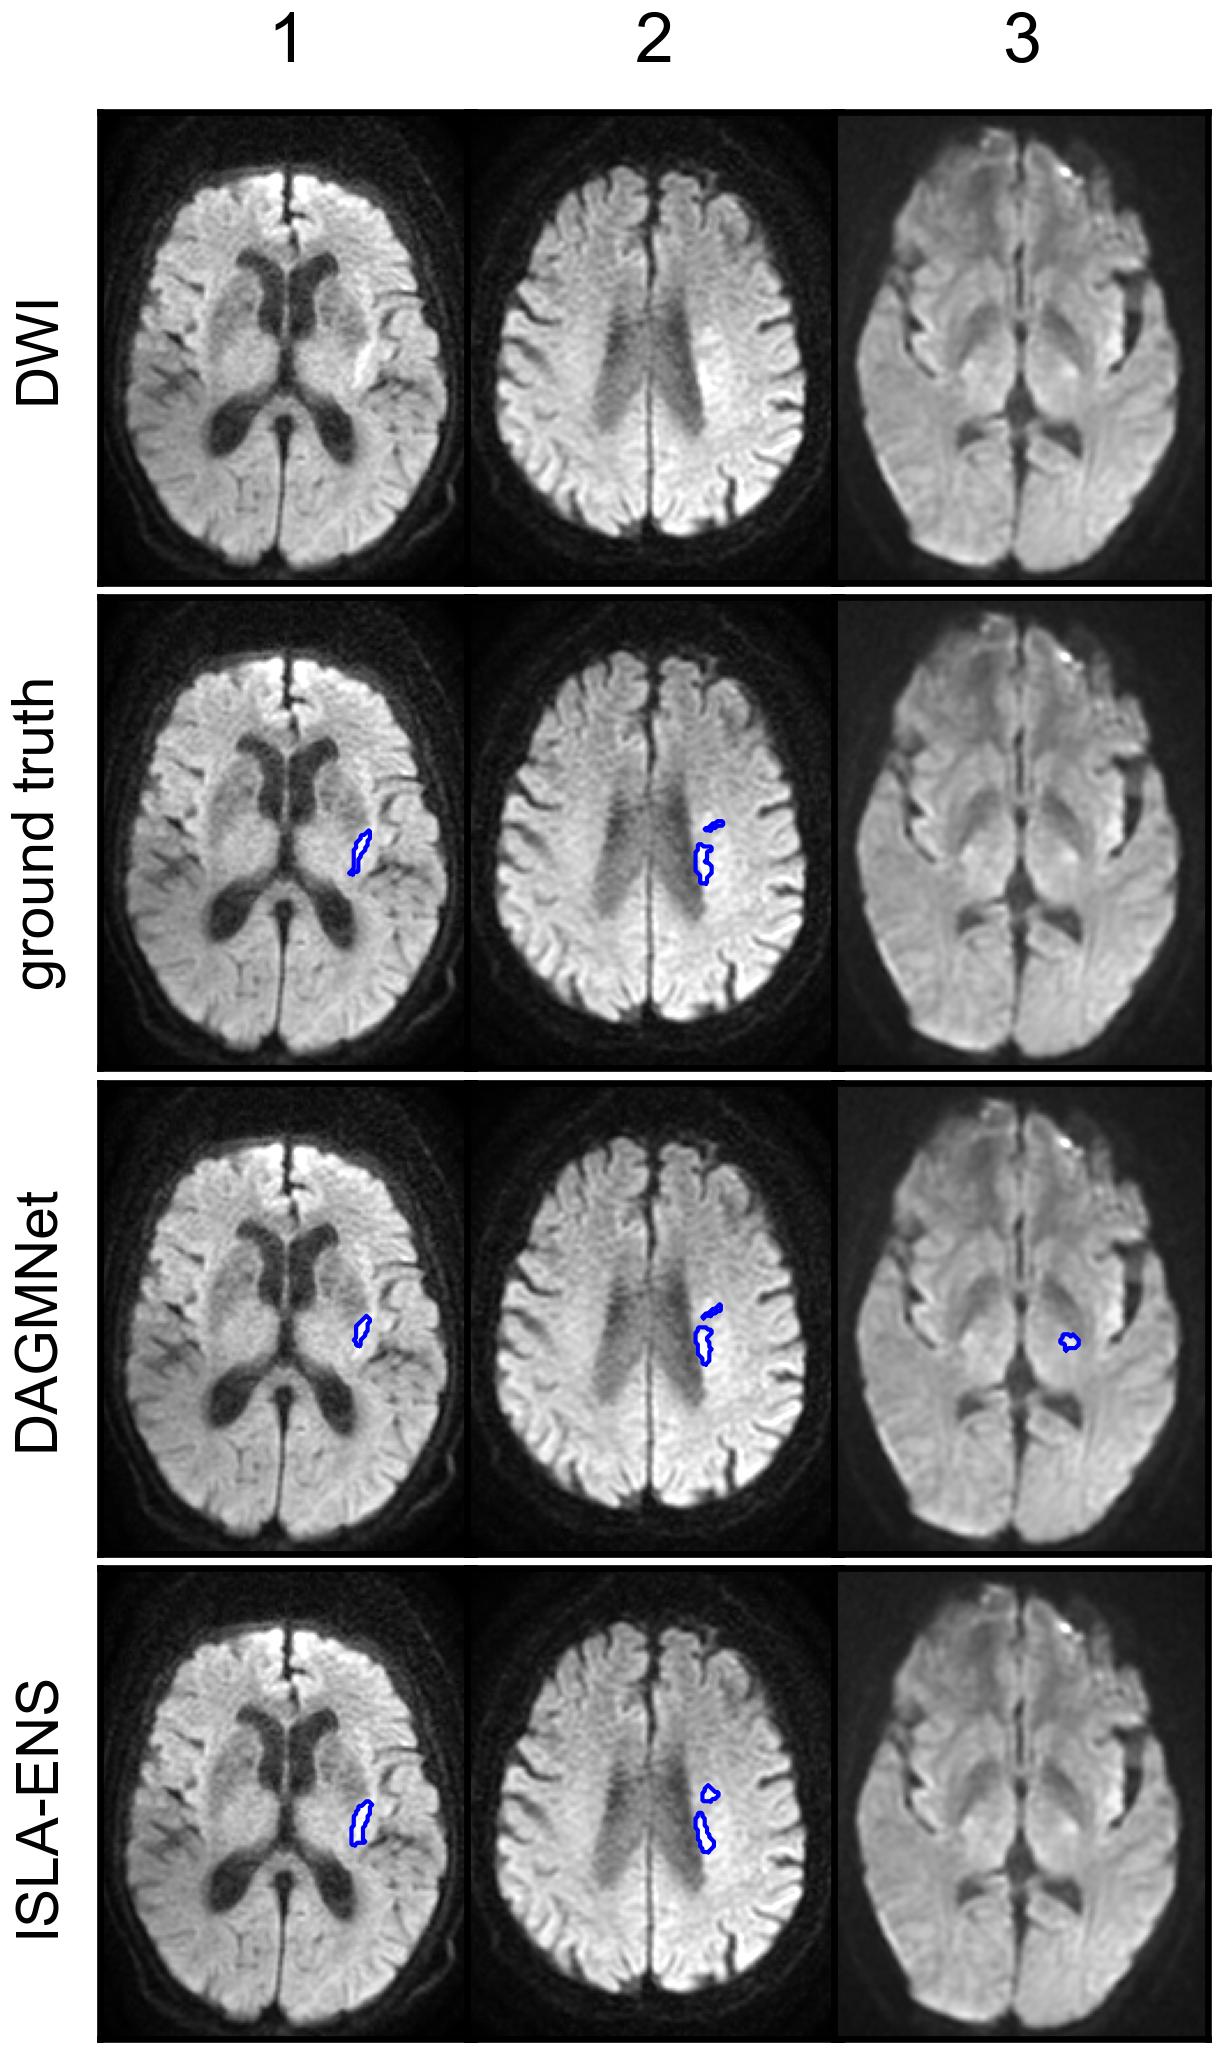

We conducted qualitative comparisons between the best-performing SOTA and ISLA models.

First, within each lesion-size group, we selected for visualization axial slices from the volumes closest to the first, second, and third quartiles of the DSC difference between the two models, excluding cases whose DSC deviated by more than 0.2 from the respective model-specific median within the group.

Figure 4 shows representative examples of segmentations from the test set with DAGMNet and ISLA-ENS, the best SOTA and ISLA models according to the test set case-level ranking (Table 5).

In cases 1 and 2 of Figure 4(a), both models successfully detected the lesions; however, DAGMNet slightly underestimated the lesion extent in case 1. In case 3, a corticospinal tract anisotropy artifact resulted in FPs for DAGMNet.

Cases 1 and 3 of Figure 4(b) further illustrate underestimation of lesion extent by DAGMNet, whereas ISLA-ENS produced segmentations closely matching the manual annotations. In case 2, both models generated FPs due to magnetic-susceptibility artifacts near the nasal region.

In Figure 4(c), case 1 shows accurate delineation of the lesion by both models, with no FPs induced by the inhomogeneity artifact. Case 2 demonstrates a missed small cerebellar lesion by ISLA-ENS. In case 3, both models correctly localized the lesion, but DAGMNet again produced FPs caused by magnetic-susceptibility artifacts around the nose.